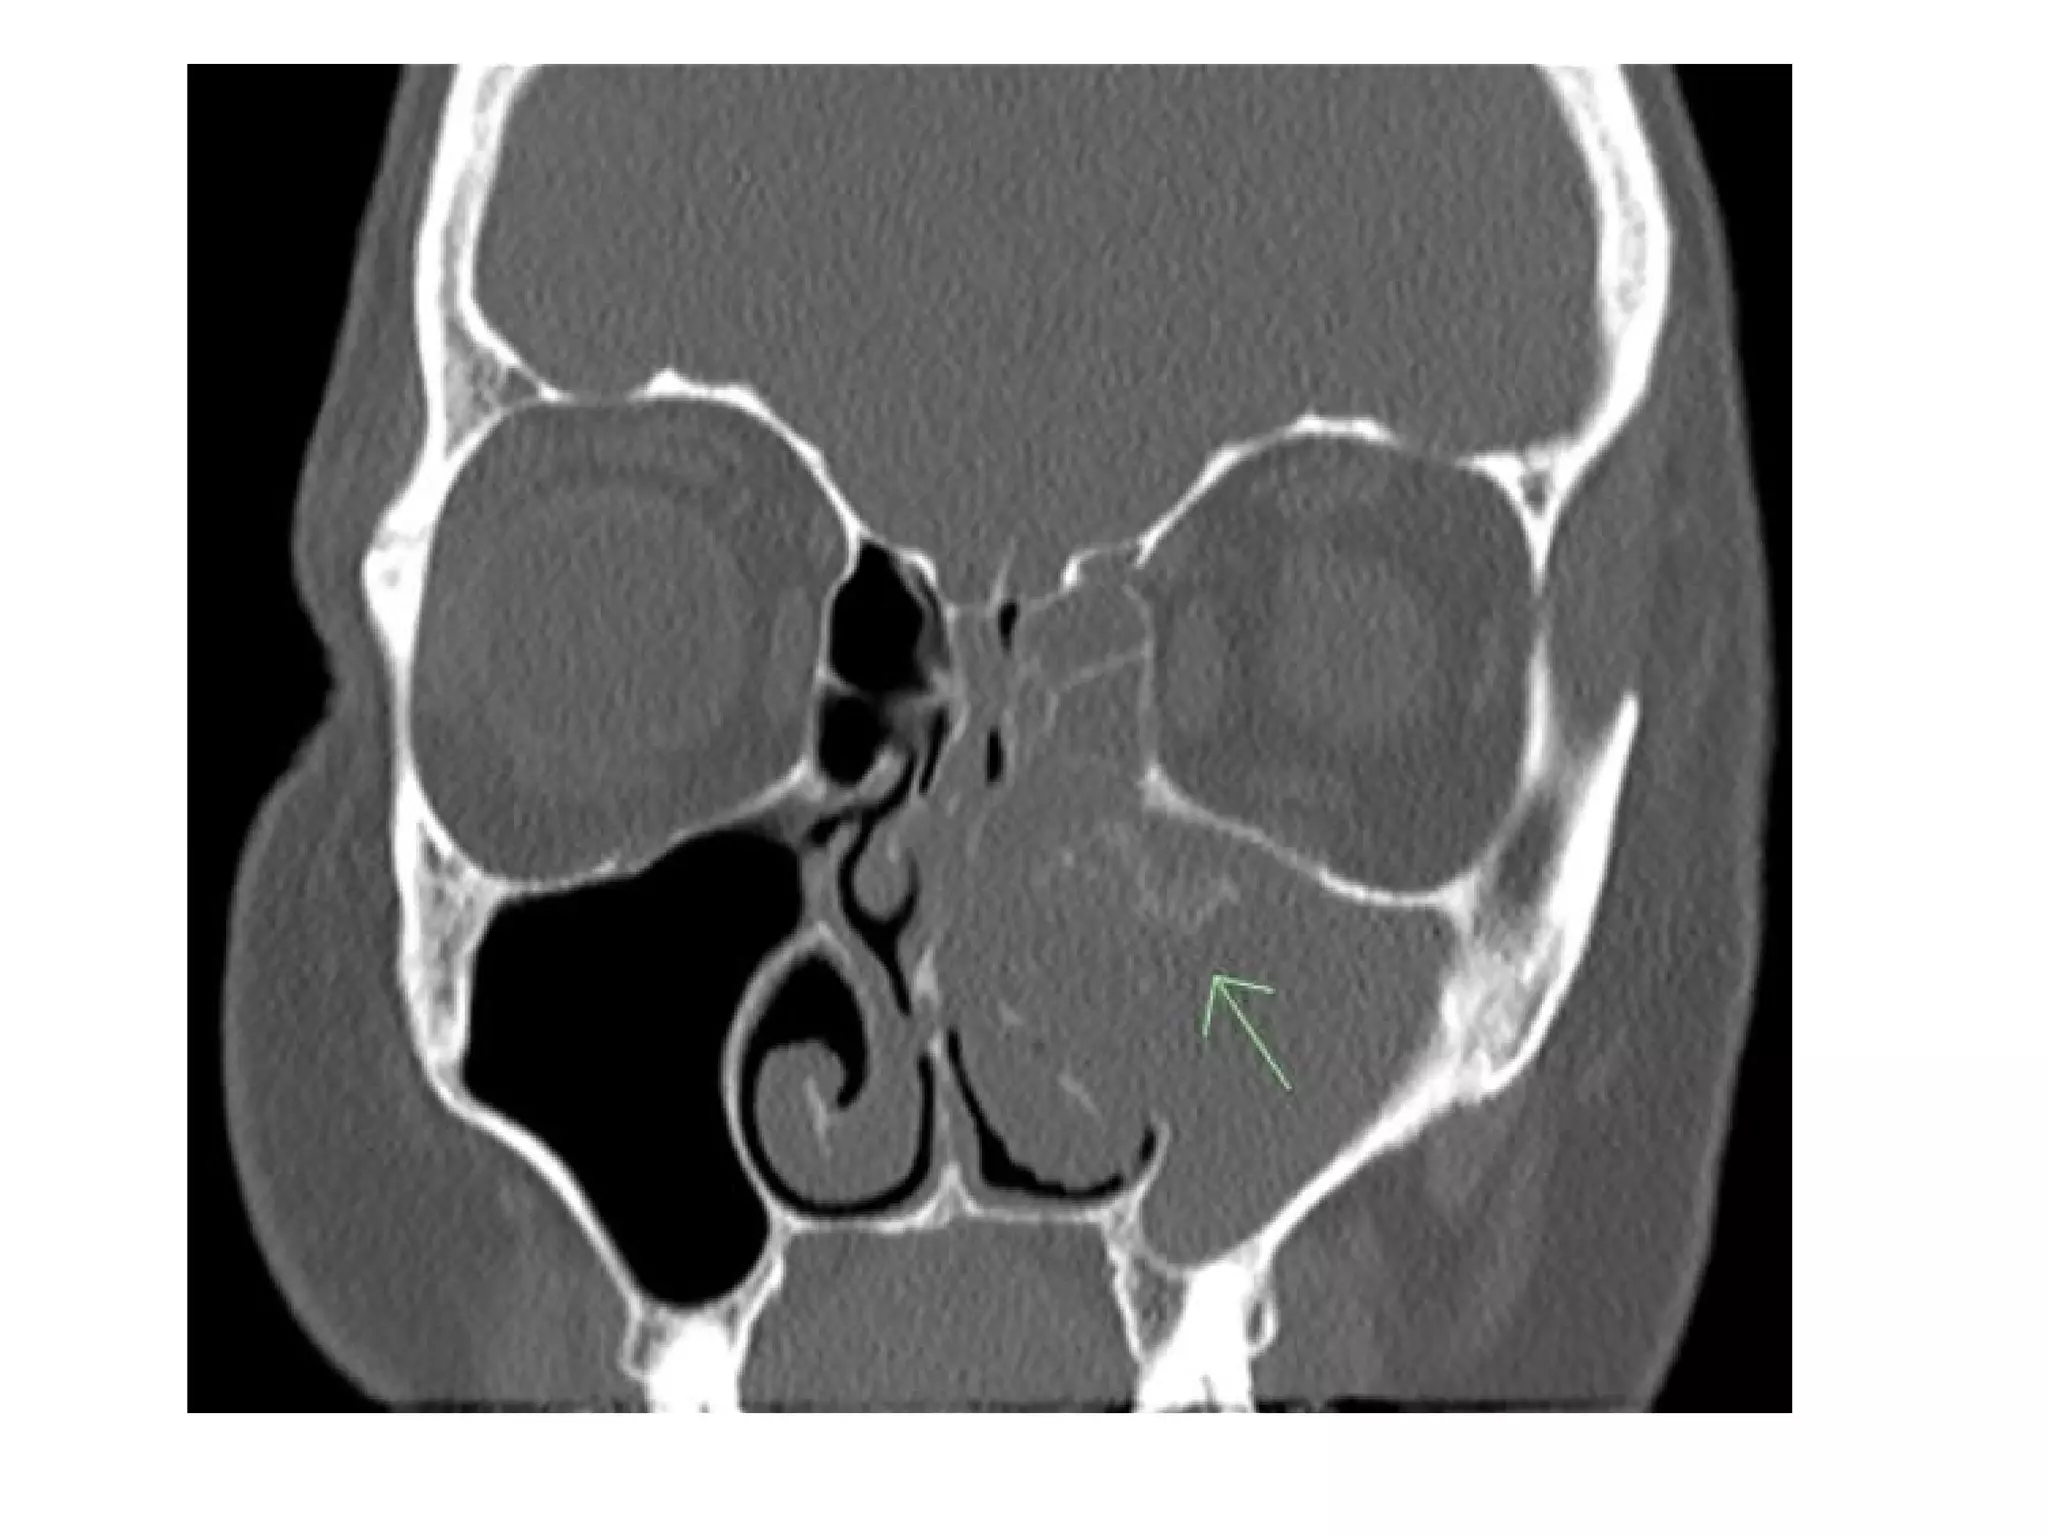

Maxillary sinus squamous cell carcinoma, (a) Axial CT shows erosion of the

lateral nasal wall and lacrimal duct (arrow) and growth into the middle

meatus (asterisk) consistent with a T2 cancer, (b) Coronal CT in another

patient with a carcinoma mimicking a nasal polyp, however, the lateral nasal

wall is eroded (arrow)